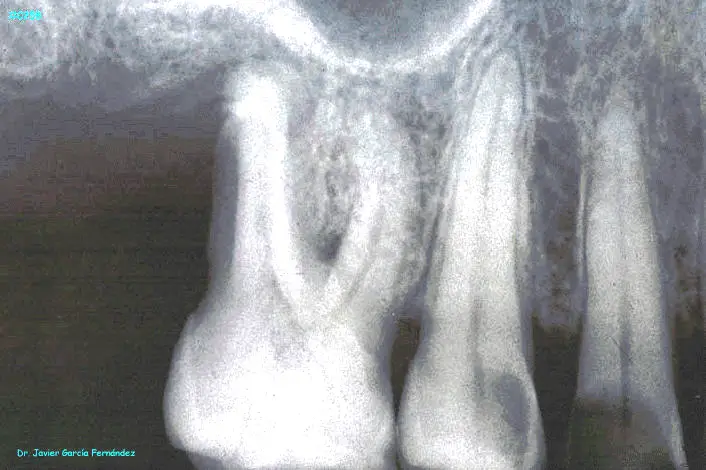

ATLAS DE CIRUGIA PERIODONTAL

image316